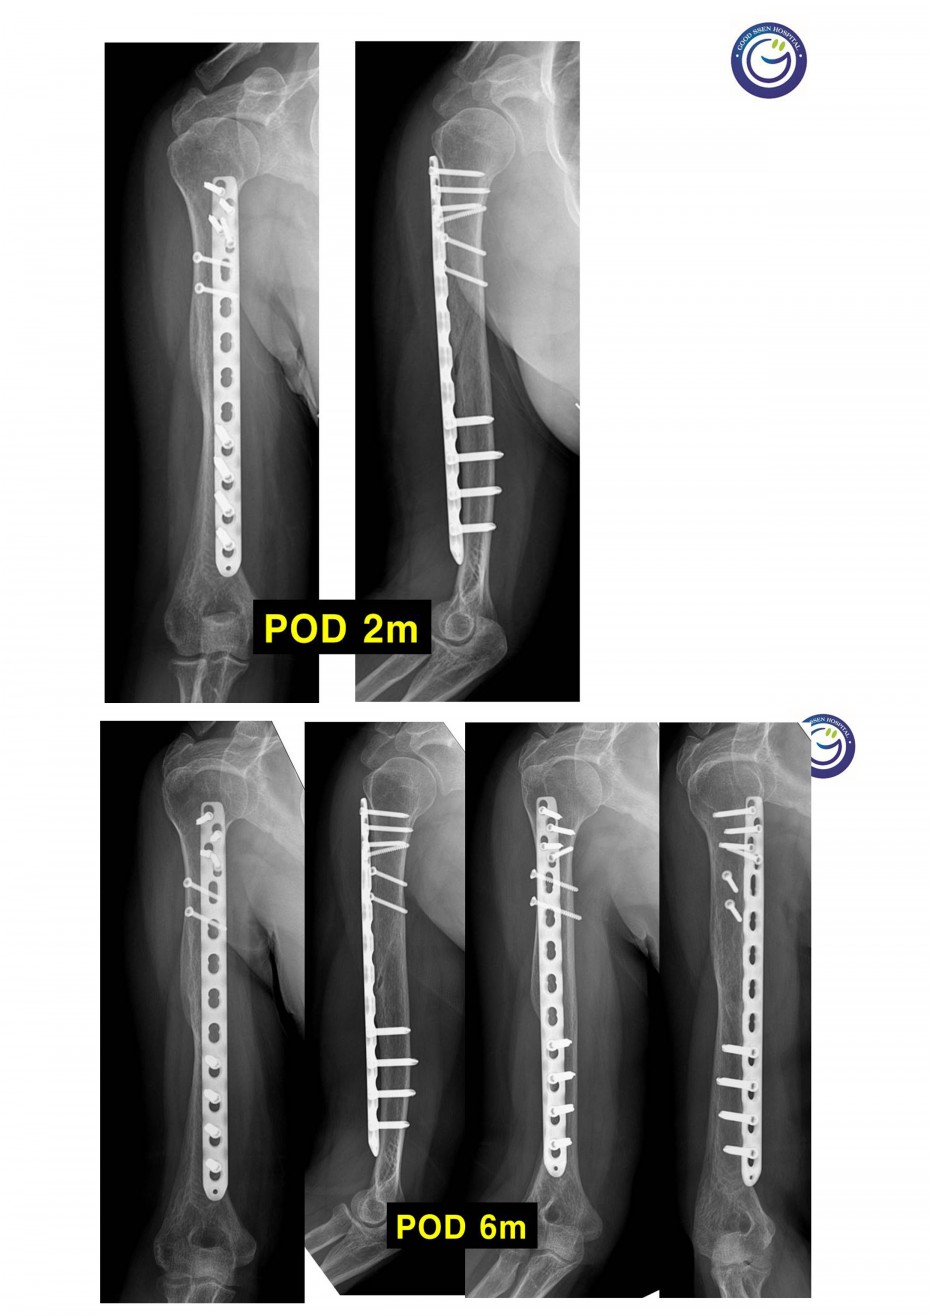

관절을 침범하는 심한 분쇄골절

절개없이 고정하는 최소침습적 고정방법 (MIPO)